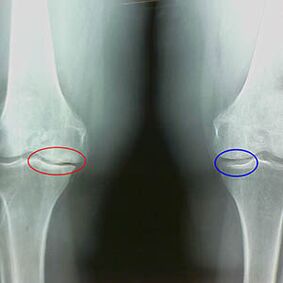

A determinação do grau de artrose ocorre por X -rayrevelando a participação no processo patológico das estruturas ósseas. Sua mudança indica que o sistema muscular está em um desequilíbrio há 5 a 10 anos. Como regra, pessoas Por vários anos eles sofrem dores doloridas.

O segundo estágio da artrose é considerado fácil. A radiografia revela esporões ósseos significativos, mas a cartilagem não é afetada. A quantidade de líquido sinovial é reduzida, mas os sintomas de dor aparecem após uma longa caminhada e corrida, rigidez na articulação e dor ao dobrar e na posição nos joelhos.

Raios X -X -X da segunda etapa da artrose do joelho:

- as bordas pontiagudas dos tubérculos inter -crus na tíbia, onde o ligamento em forma de cruz é anexado;

- estreitando a lacuna conjunta no lado medial;

- As bordas pontiagudas dos côndilos dos ossos nos lados mediais, com menos frequência no lateral - dependendo do desenvolvimento da deformação da articulação Valgus ou Varior.

Para a segunda etapa em Larsen O estreitamento da lacuna conjunta em mais de 50% é característica, mas isso só pode ser verificado na dinâmica ou comparação com uma junta diferente.